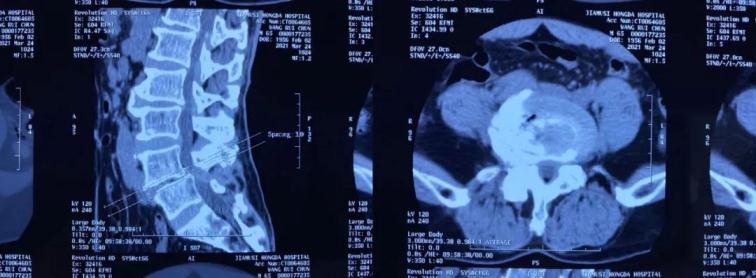

患者王某,男,65歲,腰痛伴右下肢麻痛1年,坐起及行走時(shí)疼痛明顯加重,行走不足100米即疼痛難忍需要休息,保守治療無效,嚴(yán)重影響生活質(zhì)量。慕名來到我院并找到喬院長(zhǎng)尋求治療?;颊呷朐汉?,經(jīng)過喬院長(zhǎng)認(rèn)真細(xì)致的檢查,診斷為:腰椎管狹窄、腰椎滑脫。

術(shù)前CT